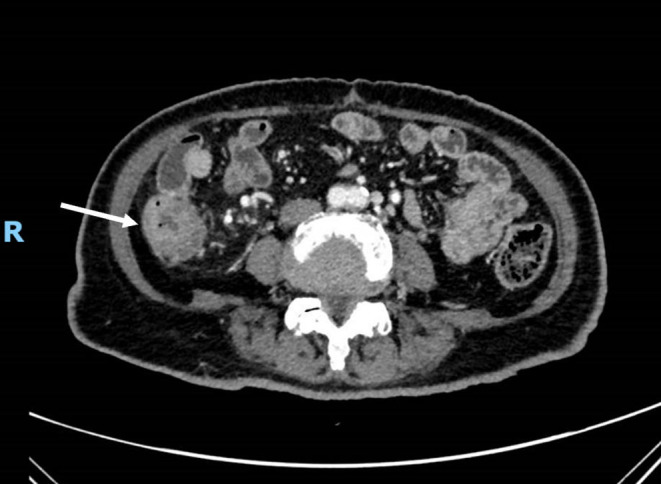

Clostridioides difficile infection (CDI) is a major healthcare-associated concern, particularly in the elderly. While CDI typically manifests as toxin-mediated colitis, hematogenous dissemination leading to bacteremia is relatively rare and associated with high mortality. We report an unusual case of C. difficile bacteremia in an octogenarian female patient occurring shortly after right hemicolectomy for ascending colon adenocarcinoma. This critically ill patient presented with bloodstream infection in the ICU following surgery. Multiple risk factors converged, including advanced age, extensive colorectal surgery with mucosal disruption, malignancy, and broad-spectrum antibiotic exposure. Blood culture identification required specific anaerobic processing. Combined intravenous and high-dose oral vancomycin therapy, guided by rapid microbiological confirmation, led to successful resolution of the bacteremia. This case underscores the potential for life-threatening C. difficile bacteremia in vulnerable elderly patients post-colorectal cancer surgery, highlights the diagnostic challenges (necessitating anaerobic blood cultures), and emphasizes the critical importance of early suspicion, aggressive multimodal therapy, and meticulous antimicrobial stewardship in this high-risk population. It serves as a crucial reminder of this devastating complication.